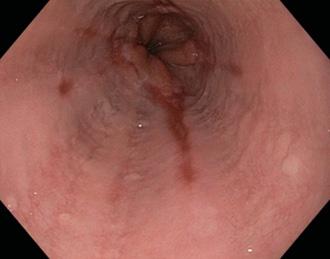

Esófago de Barrett

Metaplasia intestinal de la mucosa esofágica inducida por reflujo crónico

♦Epitelio poliestratificado plano → monoestratificado cilíndrico (ENARM 2007) (ENARM 2002)

♦La zona de transformación fisiológica (línea Z) entre el epitelio escamoso y columnar se desplaza hacia arriba.

Lesión premaligna que requiere una estrecha vigilancia.

♦Metaplasia → displasia → adenocarcinoma

Diagnóstico: endoscopía + biopsia

Figura 6. Esofagitis erosiva. Son visibles múltiples Figura 7. Esófago de Barret es una lesión premalgina. Metaplasia → displasia → adenocarcinoma (tercio inferior del esófago)

Terapia con IBP

♦ Continúe la terapia de mantenimiento a largo plazo si presenta síntomas. Endoscopia con biopsias de cuatro cuadrantes en cada 2 cm del área sospechosa (mucosa de color rojo salmón)

Figura 8. Esófago de Barrett. El reflujo crónico → el ácido del estómago daña el epitelio escamoso estratificado del esófago distal → que luego se reemplaza por epitelio columnar y células caliciformes.